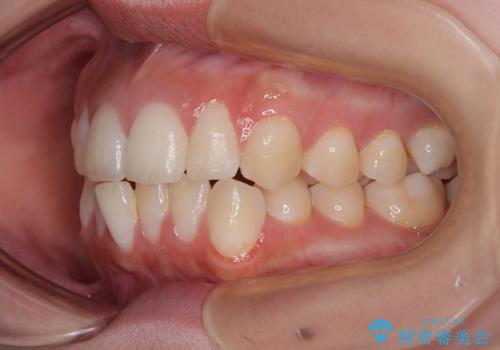

- 今回は「下の前歯のデコボコを治したい」と来院された患者様の症例をご紹介します。

診察してみると、下の前歯が並ぶためのスペースが足りないことが、歯並びがデコボコしている原因でした。

そこで今回は、以下の2つの方法を組み合わせて治療を行いました:

下の前歯の歯と歯の間をわずかに削ってスペースを作る(IPR)

奥歯を後ろに動かして、前歯が並ぶためのスペースを確保する

この計画により、デコボコだった下の前歯はしっかりと並び、わずか1年で治療を終えることができました